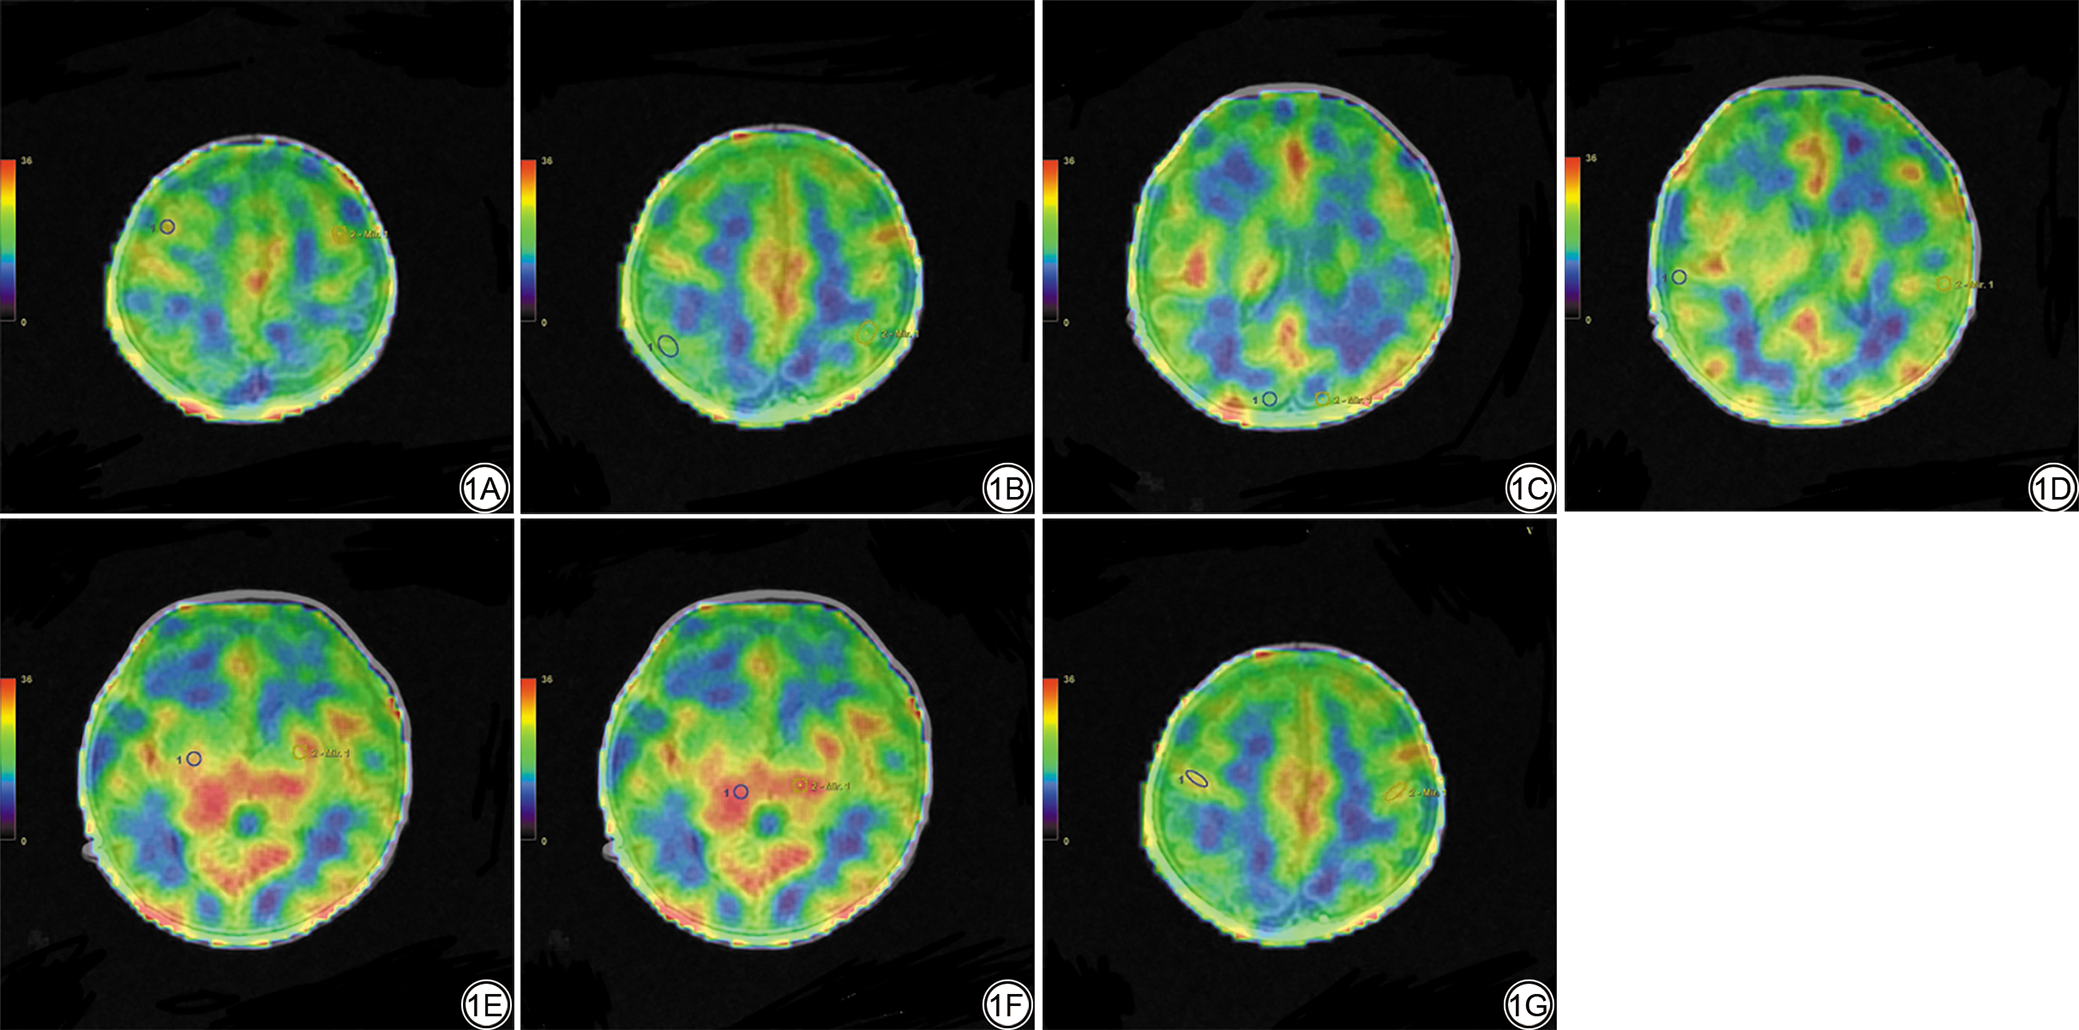

使用ADW 4.7工作站进行后处理,使用Ready View软件将Ax-T2 CUBE图像与3D-pCASL图像生成的彩图融合,在融合图像上手动勾画感兴趣区(region of interest, ROI),包括双侧额叶、颞叶、顶叶、枕叶、基底节区及丘脑,勾画层面的选择以清晰显示结构最大的层面为准,ROI的大小选择为20~40 mm2,左右两侧镜像对称,测量3次后取平均值。详见图1

图1  在融合图像上的ROI选择示意图。1A:额叶;1B:顶叶;1C:枕叶;1D:颞叶;1E:基底节区;1F:丘脑;1G:中央沟皮层。

Fig. 1  ROI selection on fused images. 1A: Frontal; 1B: Parietal; 1C: Occipital; 1D: Temporal; 1E: Thalamus; 1F: Basal ganglia; 1G: Central sulcus cortex.